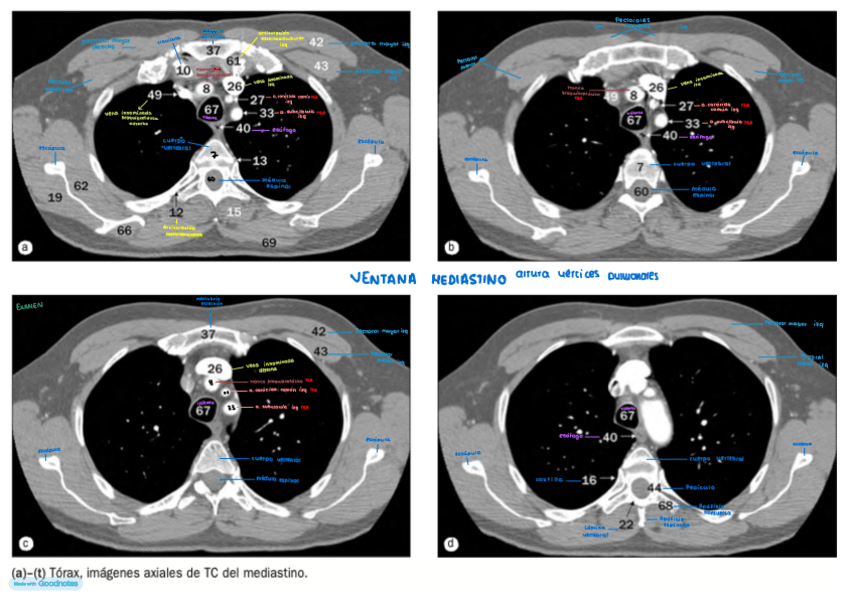

He publicado nuevos apuntes de Técnicas de Tomografía Computarizada y Ecografía: TC Y ECOGRAFÍA

IMAGENES-AXIALES-DE-TORAX-con-anatomia.pdf